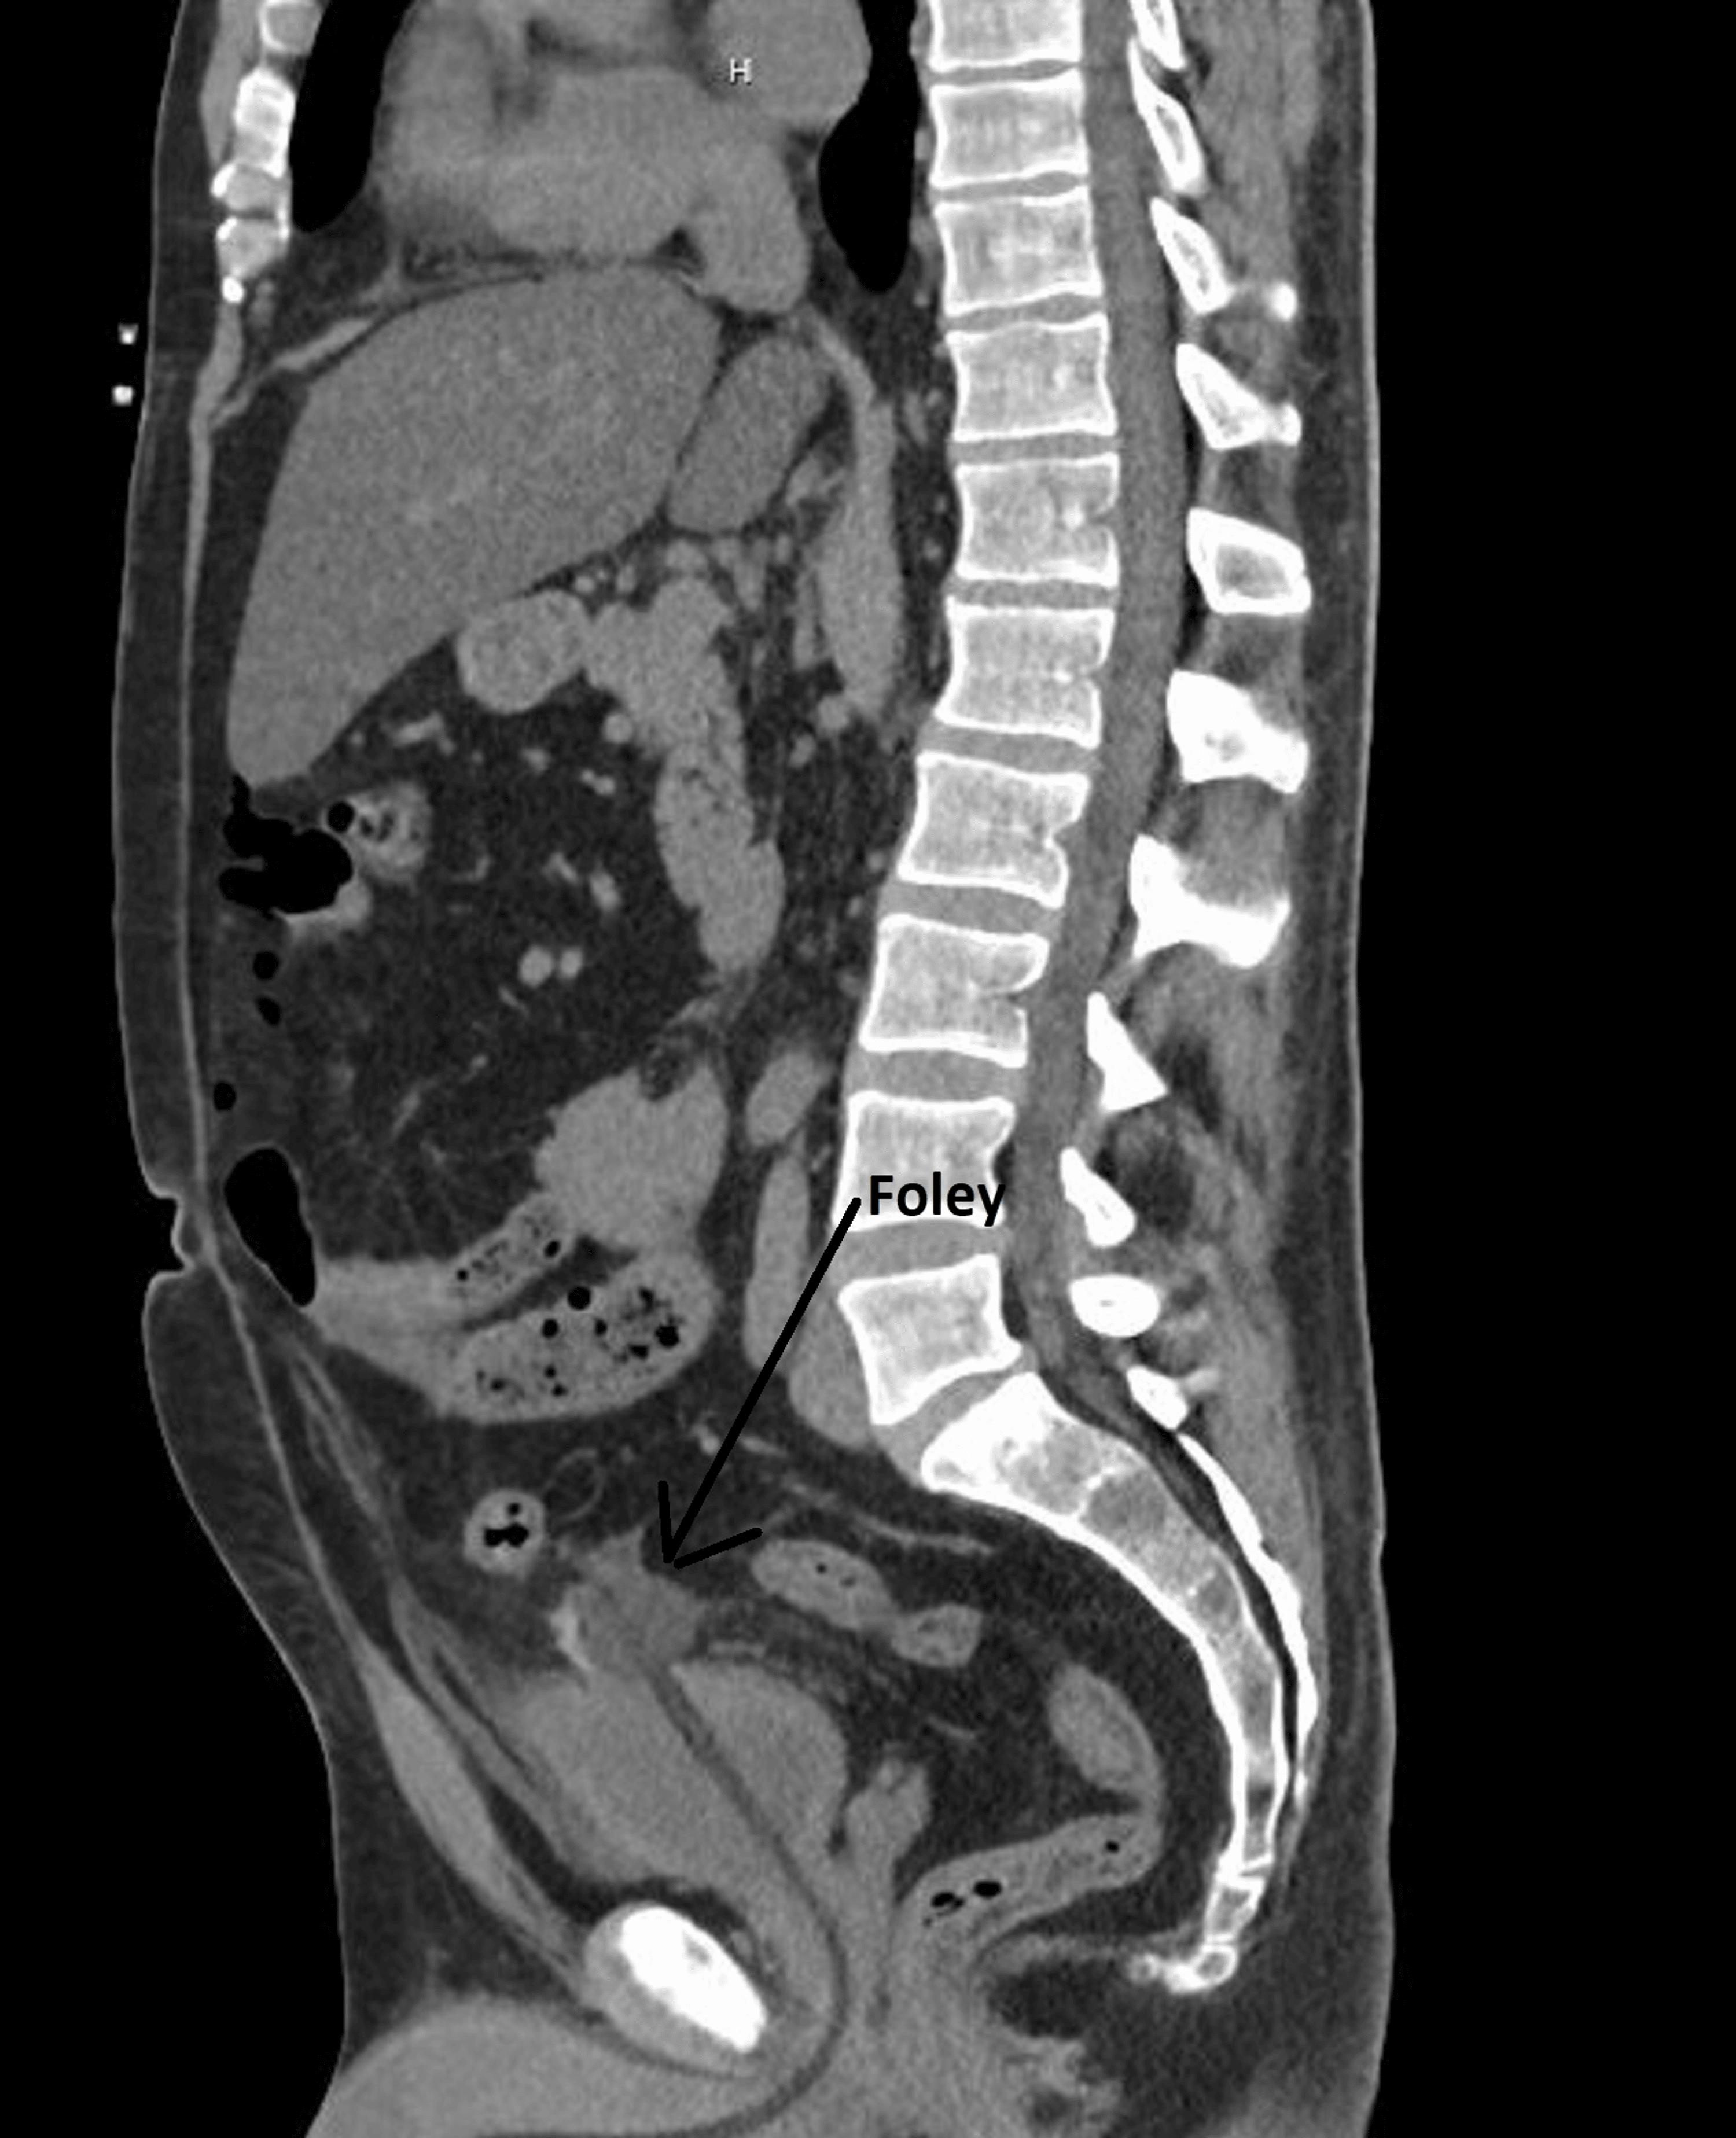

LearningRadiology Bladder Rupture, Intraperitoneal and Extraperitoneal

From www.learningradiology.com

LearningRadiology Bladder Rupture, Intraperitoneal and Extraperitoneal Can A Ruptured Bladder Be Fixed — complicated extraperitoneal bladder ruptures, such as those associated with bone fragments within the. — bladder rupture is a medical emergency that requires prompt treatment. — in general, intraperitoneal bladder ruptures do not heal on their own, so urine continues to bathe the peritoneal cavity until the injury is fixed. The bladder is a mighty strong organ. Can A Ruptured Bladder Be Fixed.